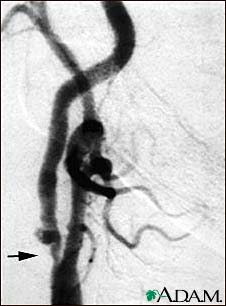

Cerebral angiography is a procedure that uses a special dye (contrast material) and x-rays to see how blood flows through the brain.

Once the catheter is in place, dye is sent through the catheter. X-ray images are taken to see how the dye moves through the artery and blood vessels of the brain. The dye helps highlight any blockages in blood flow.

Sometimes, a computer removes the bones and tissues on the images being viewed, so that only the blood vessels filled with the dye are seen. This is called digital subtraction angiography (DSA).

Contrast dye flowing out of the blood vessel may be a sign of bleeding.

Narrowed or blocked arteries may suggest:

- Blood clots causing a stroke

- Aneurysm

- Abnormal connection between the arteries and veins in the brain (arteriovenous malformation)